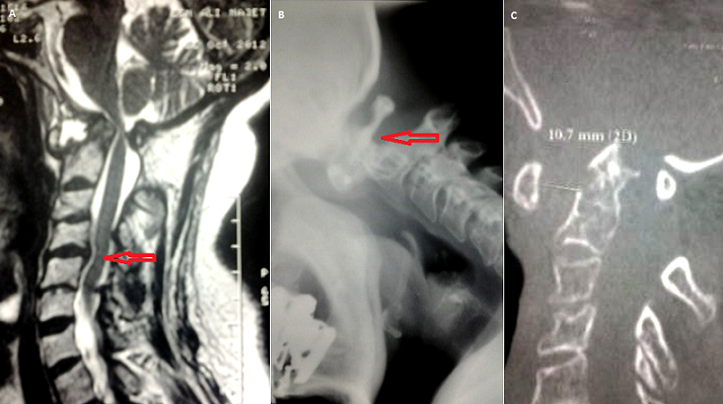

Les lésions de l'articulation atloïdo-axoïdienne peuvent émailler l'évolution de diverses pathologies rhumatismales. Elles peuvent se compliquer d'un handicap fonctionnel important et d'une atteinte neurologique parfois sévère. Nous rapportons le cas d'une patiente âgée de 55 ans, diabétique, hypertendue et suivie en Rhumatologie depuis 15 ans pour une polyarthrite rhumatoïde séropositive destructrice et déformante. Elle a été mise initialement sous MTX et SLZ, mais la polyarthrite rhumatoïde est restée évolutive d'où sa mise sous Actemra. Par ailleurs, un bilan radiologique standard demandé pour des cervicalgies révèle un diastasis C1-C2. Une TDM cervicale a montré une atteinte avancée et diffuse du rachis cervical avec une luxation C1-C2, mixte, antérieure, rotatoire et verticale et une subluxation C4-C5 et l'IRM cervicale a montré une compression médullaire pour laquelle l'abstention chirurgicale est décidée et la patiente est mise sous collier cervical. Quelques mois après, elle se présente pour une lourdeur des deux membres inférieurs avec des troubles de la marche d'installation progressive et s'étendant aux membres supérieurs. L'examen neurologique trouve une tétraparésie prédominante à gauche, un syndrome quadripyramidal et un syndrome cordonal postérieur. Ainsi, la patiente a été opérée : laminectomie C1 et ostéosynthèse. En post opératoire, lle a bénéficié de séances de rééducation fonctionnelle d'un appareillage à type d'orthèses de repos pour les deux mains et d'une attelle tibio-tarsienne gauche.